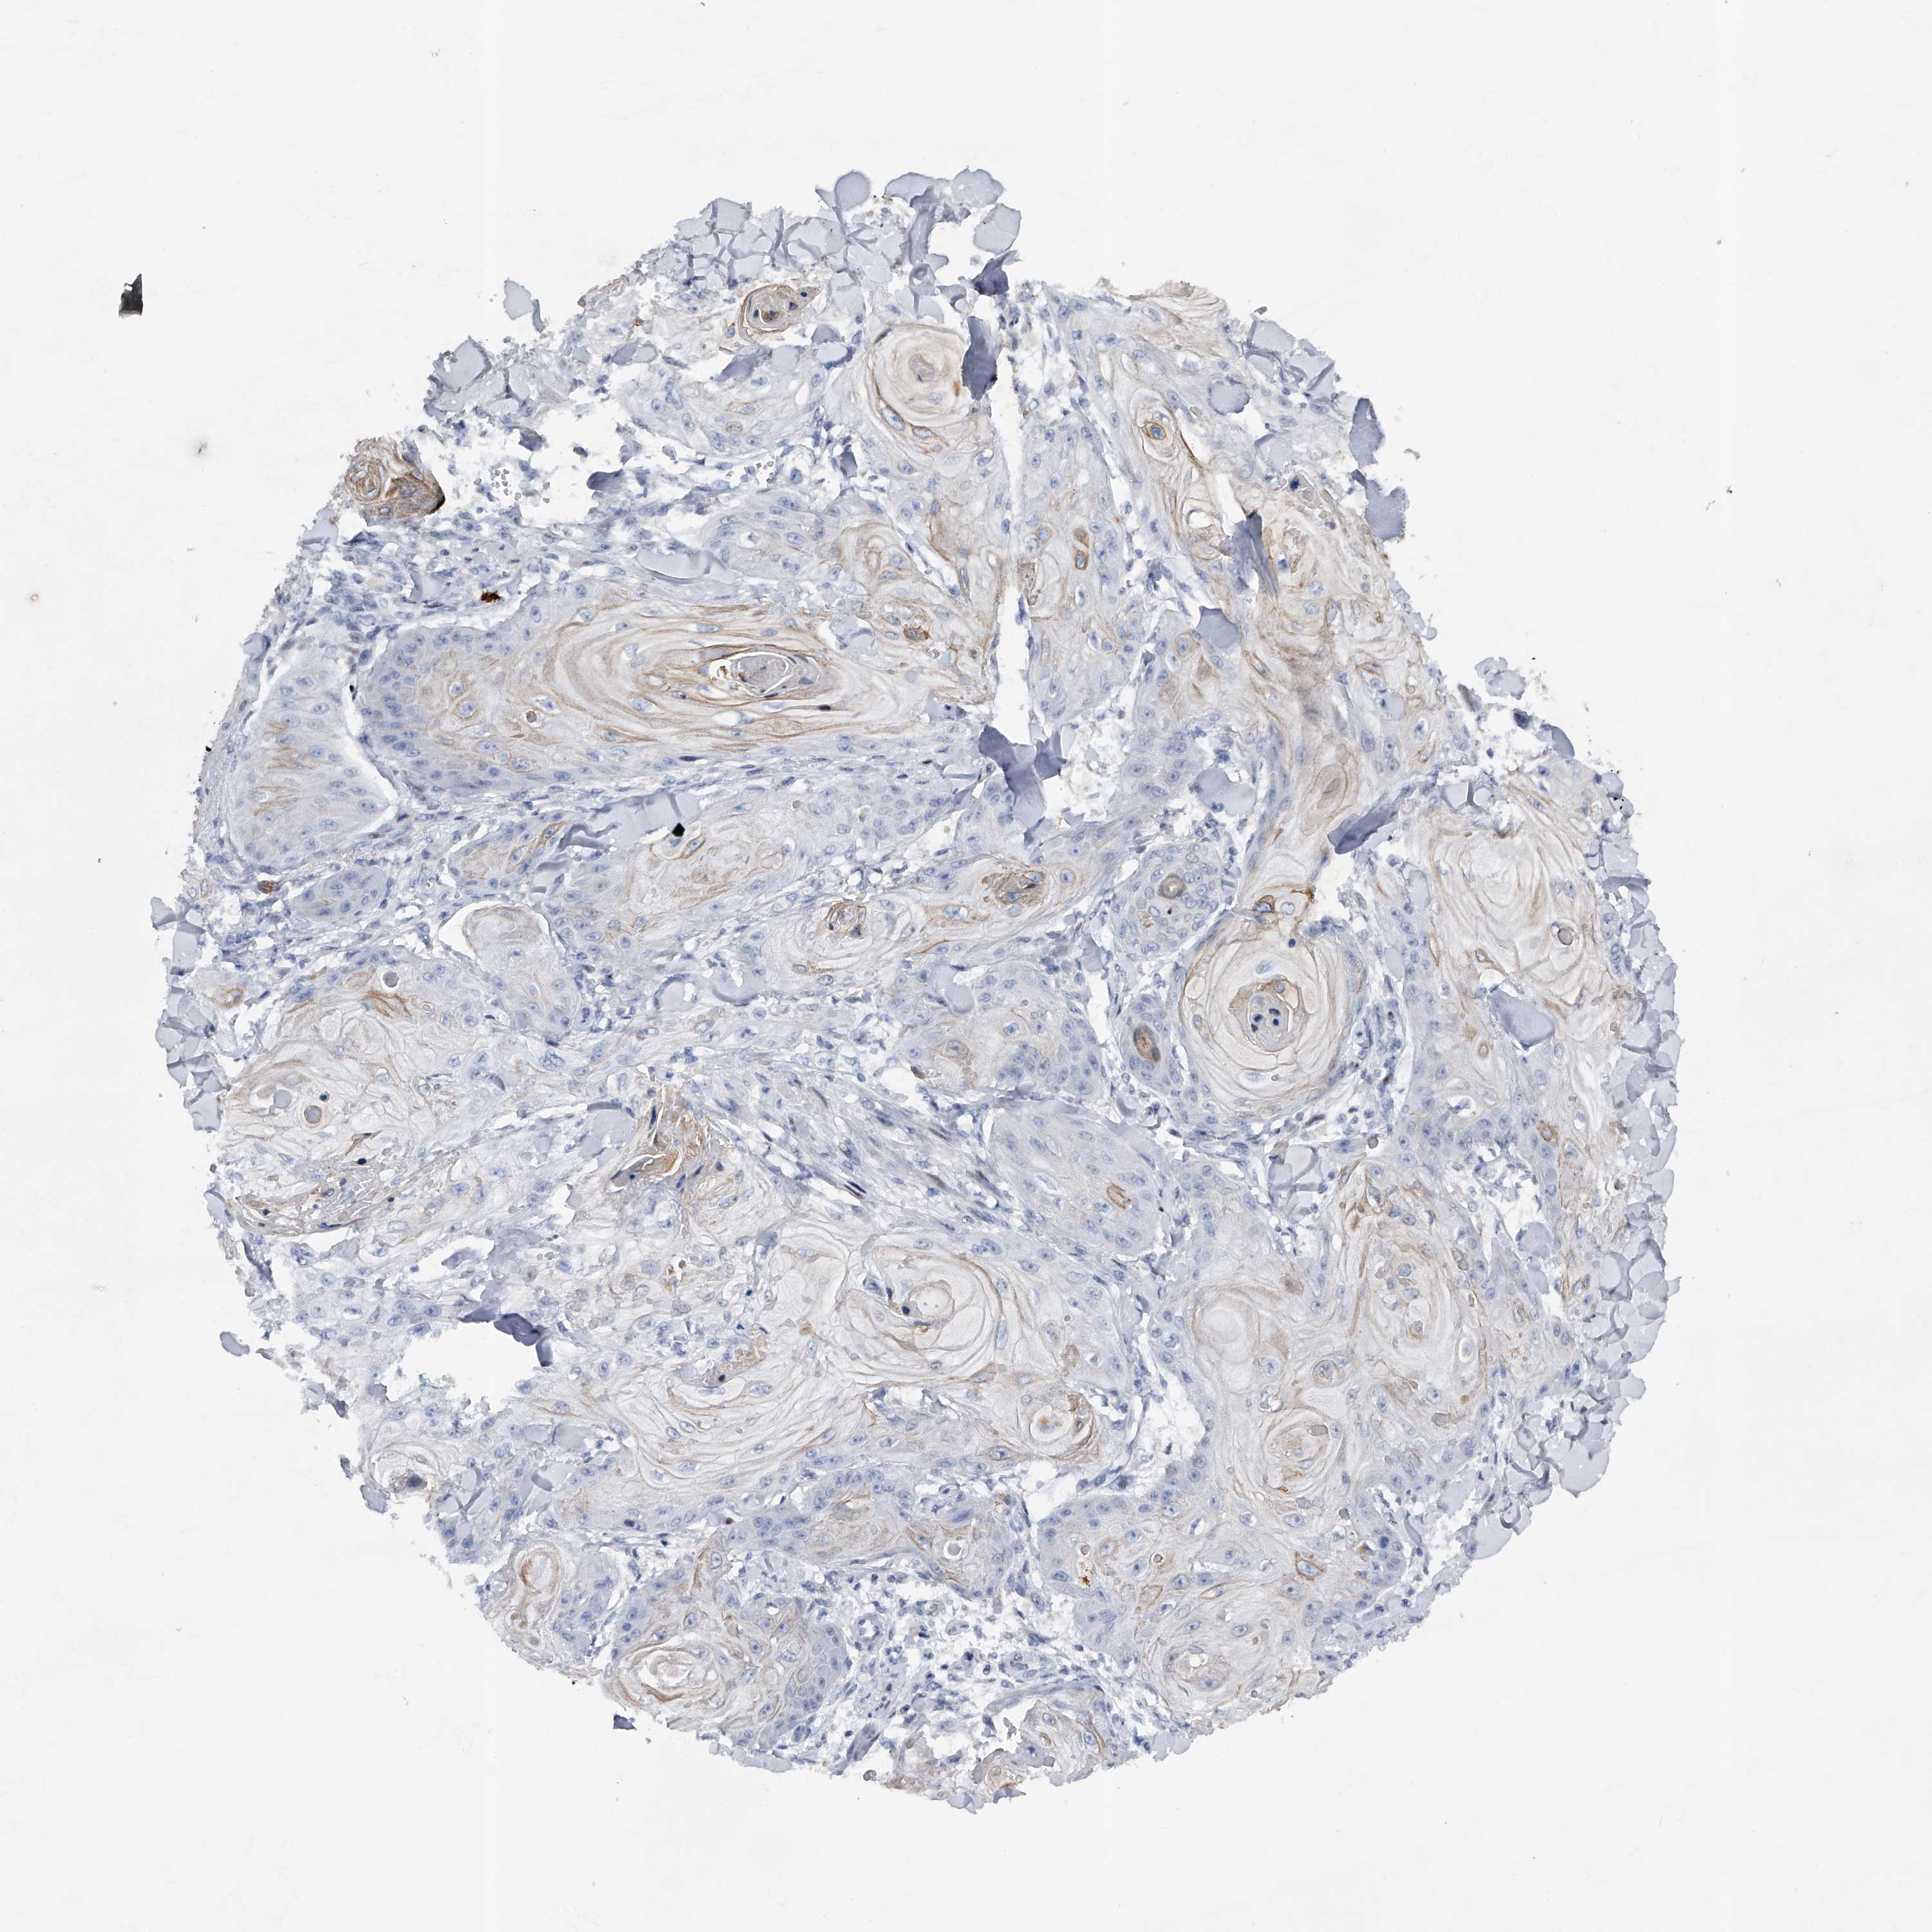

CANCER SKIN CANCER Show tissue menu

Basal cell and squamous cell cancer

SKIN CANCER - Protein expressioni

A mouse-over function shows sample information and annotation data. Click on an image to view it in a full screen mode. Samples can be filtered based on level of antibody staining by selecting one or several of the following categories: high, medium, low and not detected. The assay and annotation is described here.

Each image is clickable and will lead to virtual microscopy that enables deeper exploration of all samples and also displays staining intensity scores, fraction scores and subcellular localization as well as patient and tissue information for each sample.

Antibody HPA030107

Squamous cell carcinoma, NOS